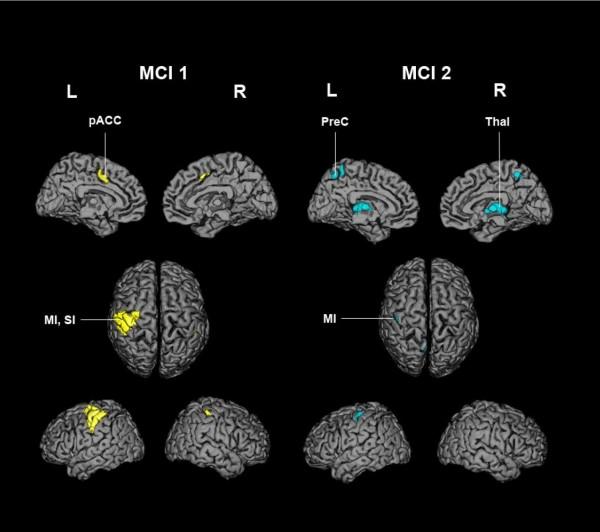

Two independent mean component images emerged. Each included the primary sensorimotor cortex contralateral to the manipulating hand. The region extended to the premotor cortex in MCI 1, whereas it was restricted to the hand area of the primary sensorimotor cortex in MCI 2. MCI 1 showed bilateral involvement of the paralimbic anterior cingulate cortex (ACC), whereas MCI 2 implicated the midline thalamic nuclei and two areas of the rostral dorsal pons.

Two distinct networks participate in tactile object manipulation as revealed by the intra- and interindividual comparison of individual scans. Both were employed by most subjects, suggesting that both are involved in normal somatosensory object discrimination.